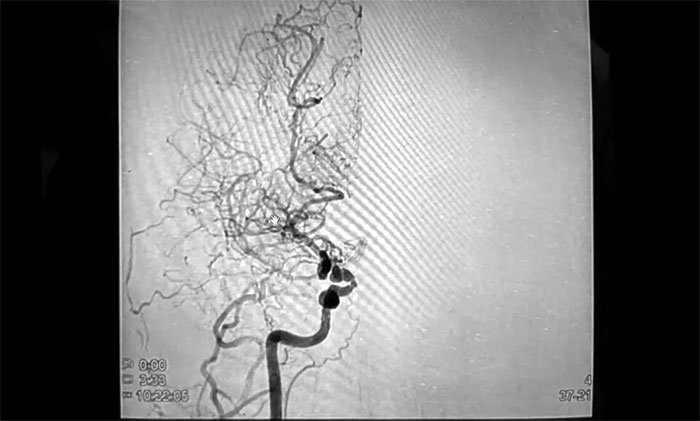

随后,住院行数字减影血管造影(DSA)后,明确诊断为“烟雾病、颅内多发动脉瘤”,这着实把她吓得不轻。

烟雾病,因颅底异常血管网在脑血管造影图像上形似“烟雾”而得名,是一种病因不明的、以双侧颈内动脉末端及大脑前动脉、大脑中动脉起始部慢性进行性狭窄或闭塞为特征,并继发颅底异常血管网形成的一种脑血管疾病。

▲ 右侧中动脉狭窄,异常血管网形成